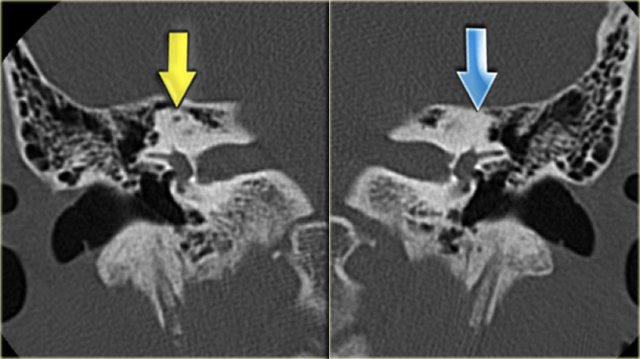

On the left a 16-year old boy, examined preoperatively for a cholesteatoma of the right ear.

As a coincidental finding, there is a plump lateral semicircular canal (yellow arrow) and an absence of the superior canal (blue arrow).

In the expected position of the superior canal only a bump is seen.

The posterior canal is normal.